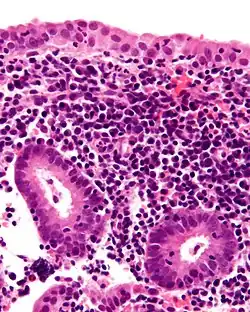

| Micrograph showing a chronic endometritis with the characteristic plasma cells. Scattered neutrophils are also present. H&E stain. | |

Chronic endometritis is characterized by the presence of plasma cells in the stroma. Lymphocytes, eosinophils, and even lymphoid follicles may be seen, but in the absence of plasma cells, are not enough to warrant a histologic diagnosis. It may be seen in up to 10% of all endometrial biopsies performed for irregular bleeding. The most common organisms are Chlamydia trachomatis (chlamydia), Neisseria gonorrhoeae (gonorrhea), Streptococcus agalactiae (Group B Streptococcus), Mycoplasma hominis, tuberculosis, and various viruses. Most of these agents are capable of causing chronic pelvic inflammatory disease (PID). Patients with chronic endometritis may have an underlying cancer of the cervix or endometrium (although an infectious cause is more common). Antibiotic therapy is curative in most cases (depending on the underlying cause), with fairly rapid alleviation of symptoms after only 2 to 3 days. Women with chronic endometritis are also at a higher risk of pregnancy loss, and treatment for this improves future pregnancy outcomes.[17][18]